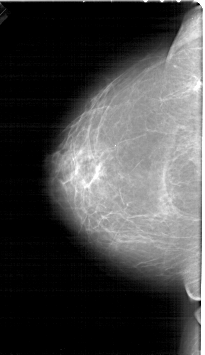

A_1452_1.RIGHT_MLO

RIGHT_MLO LINES 6871 PIXELS_PER_LINE 4276 BITS_PER_PIXEL 12 RESOLUTION 43.5 OVERLAY